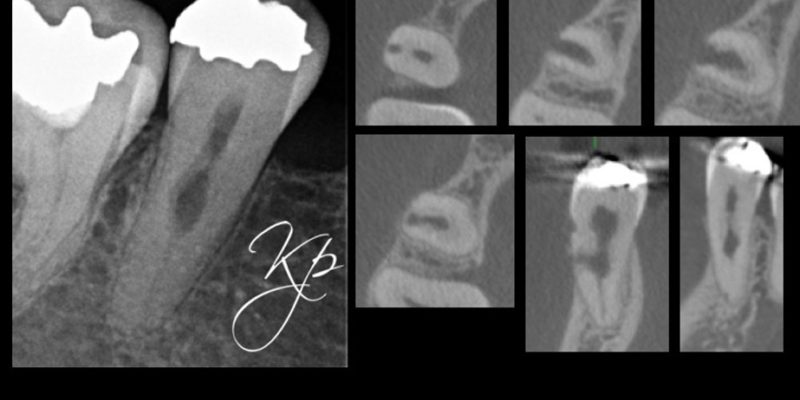

Figure 5: From the PA radiograph LR5 has the classical appearance of internal resorption.

However, the CBCT scan shows the resorption is external cervical resorption.

The resorption starts buccally at the cervical margin. It extends down the root and spreads 360º around the root canal.

We often see this appearance because the canal is surrounded by a protective predentine layer, which is more resistant to resorption

In my opinion CBCT is essential to assess external cervical resorption lesions prior to treatment.

I carried out a clinical study (Patel et al, 2016), which showed periapical radiographs significantly underestimated the size of lesions. They also provide limited information about the location and circumferential spread.

This results in differences in the treatment plan chosen by clinicians on how to best manage the resorption.

In addition to this, not all external cervical resorption lesions follow the ‘typical’ radiographic appearance mentioned above (Figure 5). A CBCT provides crucial information to obtain successful outcome.